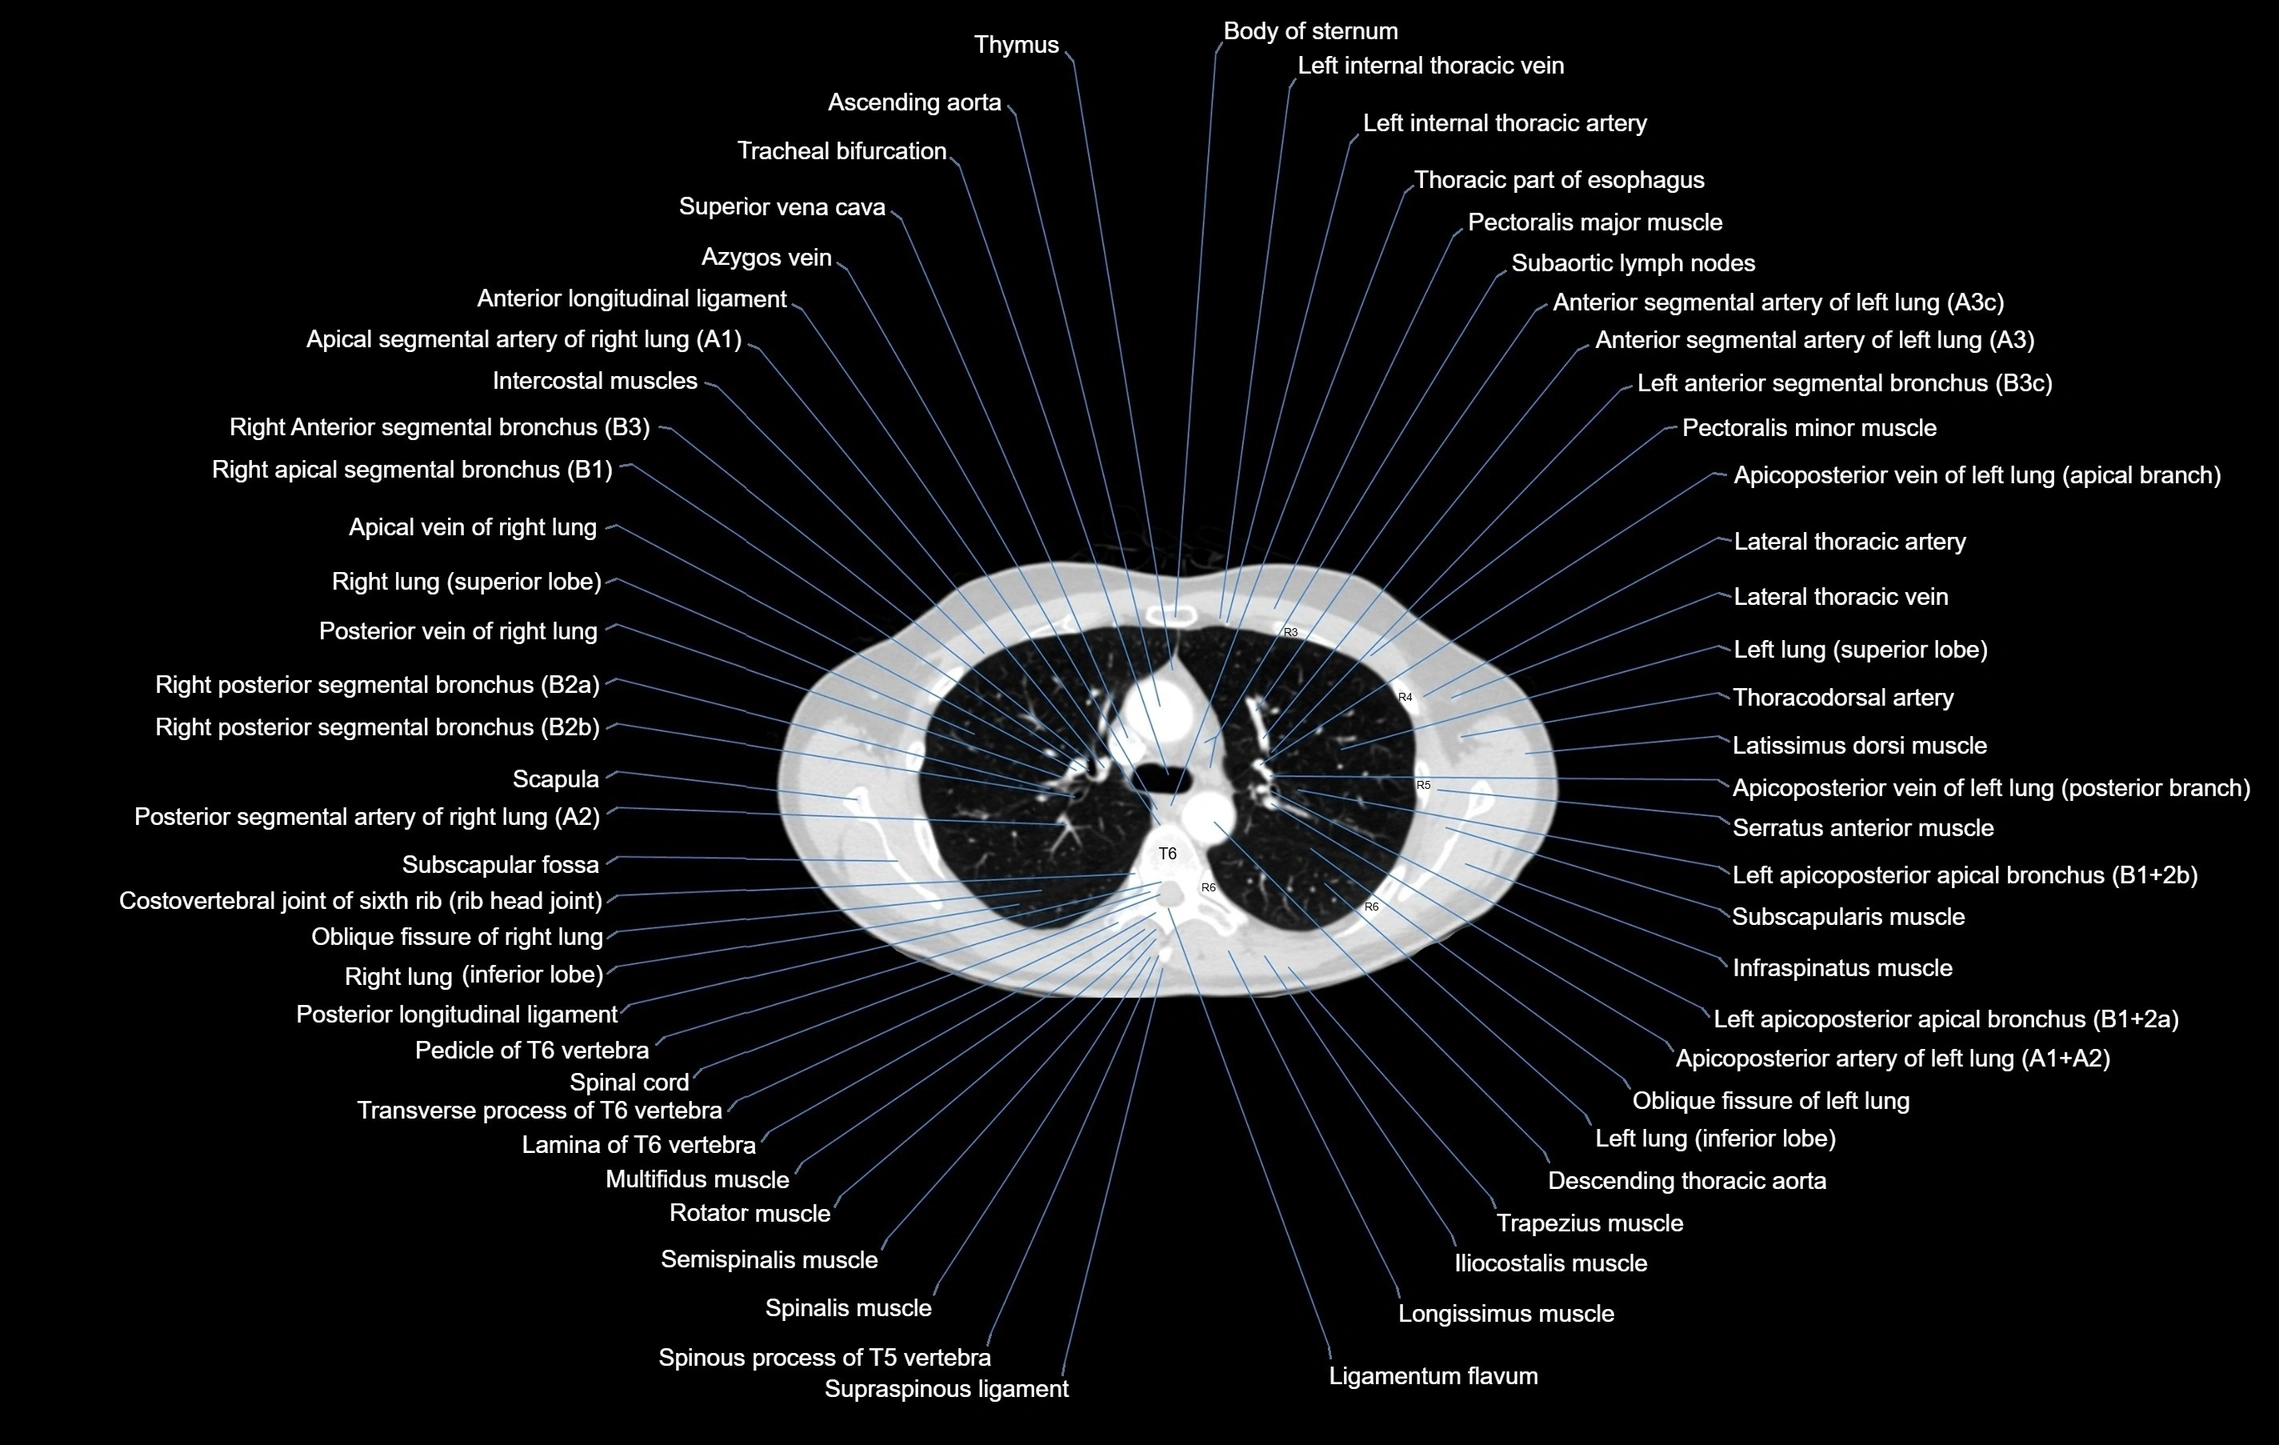

- Anterior longitudinal ligament

- Azygos vein

- Descending thoracic aorta

- Intercostal muscles

- Posterior longitudinal ligament

- Thoracic part of esophagus

- Tracheal bifurcation